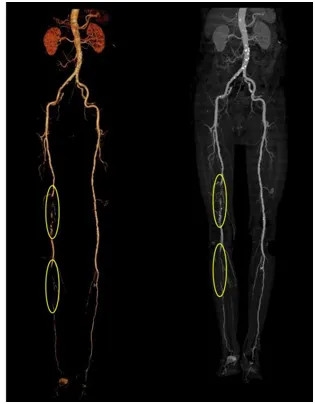

老先生在家属的陪同下到郑州大学五附院就诊,崔文军主任查体中发现老先生的右脚冰凉,轻轻触摸就疼痛难忍,腿部血管搏动也都触摸不到,于是立即收入院,主管医生李阳立即给老先生安排检查,血管CTA结果发现右腿股动脉、腘动脉和膝关节下方的动脉多处堵塞。

▲ CTA显示右侧股浅动脉、腘动脉及膝下动脉多处闭塞